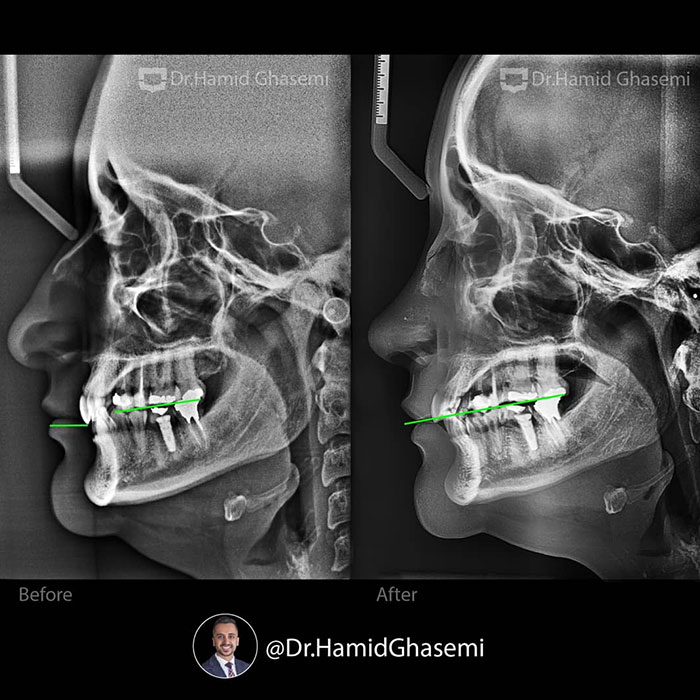

درمان ارتودنسی بدون جراحی و بدون کشیدن دندان در کیس دیپ بایت همراه با کنت اکلوزال و باکال کریدور های وسیع در مدت ۲۰ ماه انجام شد.

Non surgical and non extraction orthodontic treatment of deepbite case with occlusal cant and large buccal corridors done within 20 months.